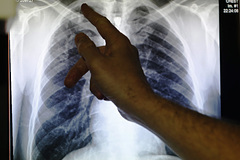

Назван способ раннего диагностирования рака по кашлю

Организация Cancer Research UK назвала кашель самым распространенным признаком рака легких. Об этом пишет Express.

Отмечается, что кашель может наблюдаться постоянно, стать болезненным или изменить «звучание». Также возможно появление крови с мокротой, что указывает на различные легочные инфекции.

К другим симптомам специалисты относят внезапно появившуюся одышку, боль в груди или плече, потерю аппетита, постоянное чувство усталости и потерю веса.

В Национальной службе здравоохранения Англии (NHS) к перечисленным признакам добавили отеки лица и шеи, а также искривление формы пальцев.

Ранее сообщалось, что боль в плечах или руках может свидетельствовать о раке легких. Также симптомами рака на ранних стадиях могут быть сухость кожи пальцев рук. Все это может возникнуть из-за проблем с кровоснабжением конечностей, вызванных повышенным давлением в кровеносных сосудах, которые связаны с легкими.